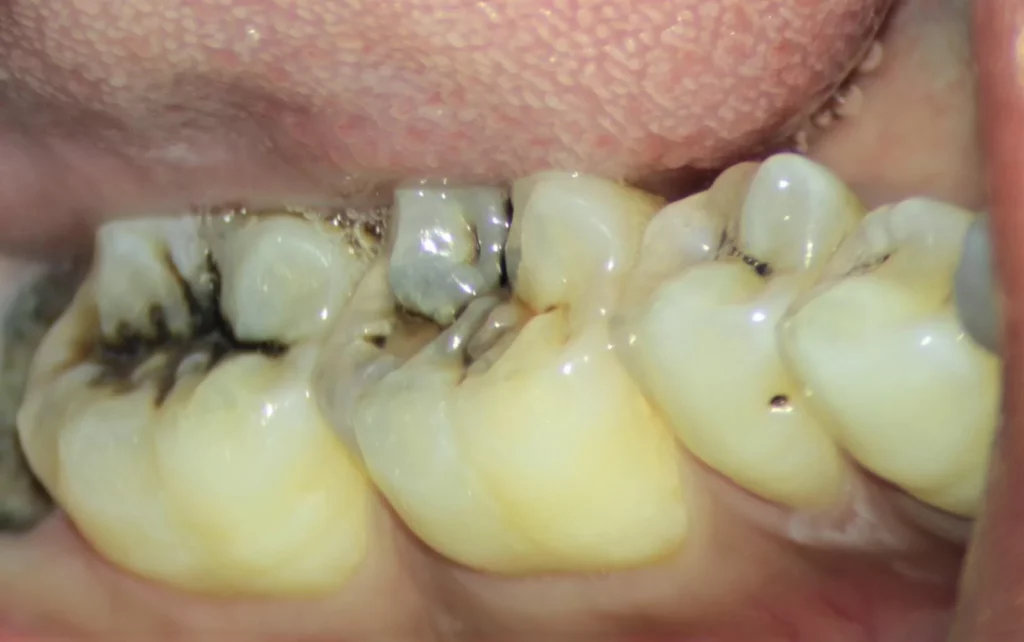

Stage Three – When Decay Reaches the Dentin Layer

Once dental caries progresses to the dentin layer, symptoms become much more noticeable. This stage marks a turning point, as the lesion advances from a superficial cavity to a deeper, more serious form of tooth decay.

By this point, enough of the enamel has been eroded to expose the underlying dentin, a sensitive tissue rich in fine nerve fibers. As a result, the patient often experiences sudden pain or sharp sensitivity when consuming cold, hot, or sweet foods and drinks.

Dentin caries spreads more rapidly than enamel caries because dentin is softer and more porous than enamel. This porosity allows acids and bacteria to penetrate deeper into the tooth structure, leading to the formation of a visible cavity or hole.

If dentin caries is not treated at this stage—typically by removing the decayed tissue and placing an appropriate dental filling—the inflammation can extend into the dental pulp, causing severe pain and complications that may require root canal treatment (endodontic therapy) or even tooth extraction.

Therefore, stage three caries is a critical warning sign that necessitates immediate consultation with a dentist to halt the progression of decay and preserve the tooth structure before it becomes irreversibly damaged.